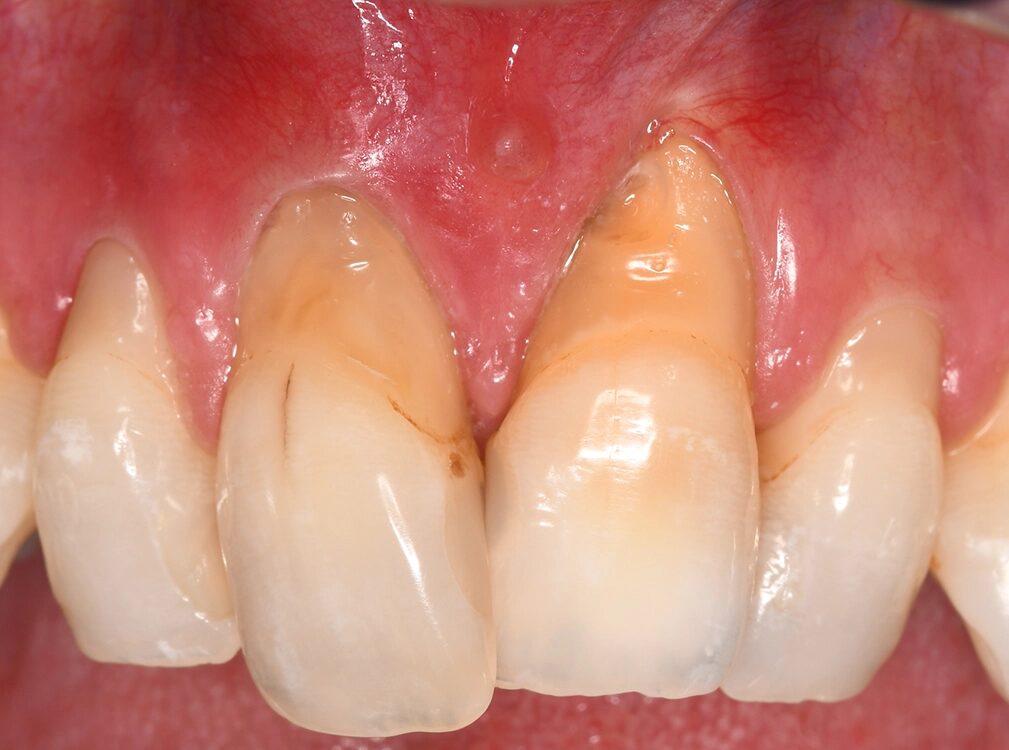

Die Ehlers-Danlos-Syndrome sind eine heterogene Gruppe von 13 unterschiedlichen Bindegewebserkrankungen, die alle durch Gelenkshypermobilitäten und überdehnbare und fragile Haut charakterisiert sind und je nach Typ mit unterschiedlichen weiteren Symptomen assoziiert sind [9]. Das parodontale Ehlers-Danlos-Syndrom (pEDS) ist das einzige der Ehlers-Danlos-Syndrome, das sich mit einer schweren Parodontitis im jugendlichen Alter, teilweise auch schon im Milchgebiss, manifestiert, da die Mutationen primär Gene der unspezifischen Immunantwort betreffen und erst in weiterer Folge die Bindegewebsschwäche verursachen [8] (Abb. 5, Abb. 6).

Die klinische Diagnose basiert auf der Trias der rasch progredienten Parodontitis im Teenageralter, dem kompletten Fehlen der befestigten Gingiva und der auffallenden Neigung zur Bildung von Hämatomen, die in zirka 80% der Betroffenen zu persistierenden Hämosiderin-Einlagerungen an den Schienbeinen führt. Die Parodontitis manifestiert sich teilweise schon im Milchgebiss, teilweise erst während der Pubertät und führt unbehandelt in wenigen Jahren zur Zahnlosigkeit. Das pEDS wird autosomal-dominant vererbt, sodass mindestens ein Elternteil ebenso an pEDS erkrankt ist; sehr selten kann es sich um eine Neumutation handeln. Die genetische Diagnose stützt sich auf die klinische Verdachtsdiagnose und wird durch den Nachweis pathogener Mutationen in den Komplement-1-Genen des C1S oder C1R gesichert.